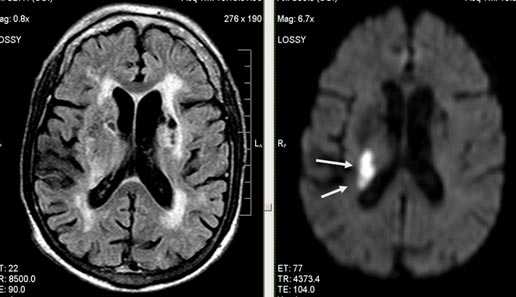

Первые часы ОНМК. Изменения в области правого островка демонстрирует только программа DW insult.

Лакунарное ишемическое ОНМК на фоне хронической сосудистой недостаточности.

Некоторые инфаркты при дисциркуляторной энцефалопатии протекают бессимптомно. Это «немые» инфаркты, которые, как правило, локализуются в глубоких отделах мозга и диагностируются только при МРТ. Этот случай показывает возможности выявление очага ограниченного ишемического ОНМК базальных ядер слева на фоне хронической ишемии.

Выраженная сосудистая энцефалопатия с наличием множественных очагов хронической ишемии, лакунарных постишемических кист. Программа ДВИ четко показывает фокус острого ОНМК в базальных ядрах справа на фоне лейкодистрофии.